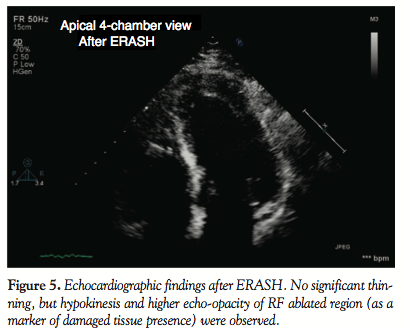

Damage of the tissue after RF ablation of septal hypertrophy was well visible on the echocardiography as a change in the tissue opacity (Figure 5). At the end of the procedure, there was no significant thinning, but hypokinesis was observed in the ablated region. Invasive measurement using the same tools and technique was then repeated at the end of the session. The peak left ventricular pressure of 203 mm Hg was not changed; however, the peak aortic pressure increased to 145 mm Hg. The procedure was stopped at this point, because further RF applications were no longer effective (there was no or minimal change of the amplitude of local electrograms at the site of ablation, indicating possible tissue edema that reduced efficacy of RF application). At the end of the procedure (total fluoroscopy time, 9.6 minutes; dose, 1.36 mGy/m2), there was neither widening of the QRS complex nor a change in the right bundle branch block morphology that was present since the ASA. No prolongation of atrioventricular conduction was observed either.

Follow-up. The patient felt well after ERASH. Continuous ECG monitoring (performed until discharge at day 8) did not reveal any atrioventricular conduction block or other arrhythmia. Maximum CK-MB mass was 1.1 µkat/L and maximum Troponin I was 3.3 µg/L (normal upper limit, 7.2 µkat/L and 0.03 µg/L, respectively). Seven days after the procedure, the ablated region exhibited similar changes of the opacity at echocardiography as at the end of the procedure, indicating damage at the ablated site (Figure 5). However SAM and LVOT gradient persisted, reaching about 50 mm Hg at rest and 100 mm Hg after nitrate provocation. The patient was therefore continued on beta-blockers. Magnetic resonance imaging (MRI) using gadolinium administration performed on day 8 after ERASH demonstrated late enhancement in two LVOT regions: the first one in the subaortic region corresponded with RF lesion sites, the second one (more midventricularly located) with scar after ASA (Figure 6). The patient was kept on his permanent medication after the procedure. At the 2-month follow-up exam, the patient reported improvement of symptoms. Dyspnea reduced to NYHA class 2 and angina CCS 1-2. Echocardiographically, the RF ablated region measured 14 mm; however, the persistent subaortic maximum was now akinetic, thus leading to a LVOT gradient reduction to 15 mm Hg. Gadolinium-contrast MRI showed findings similar to day 8 after ERASH.